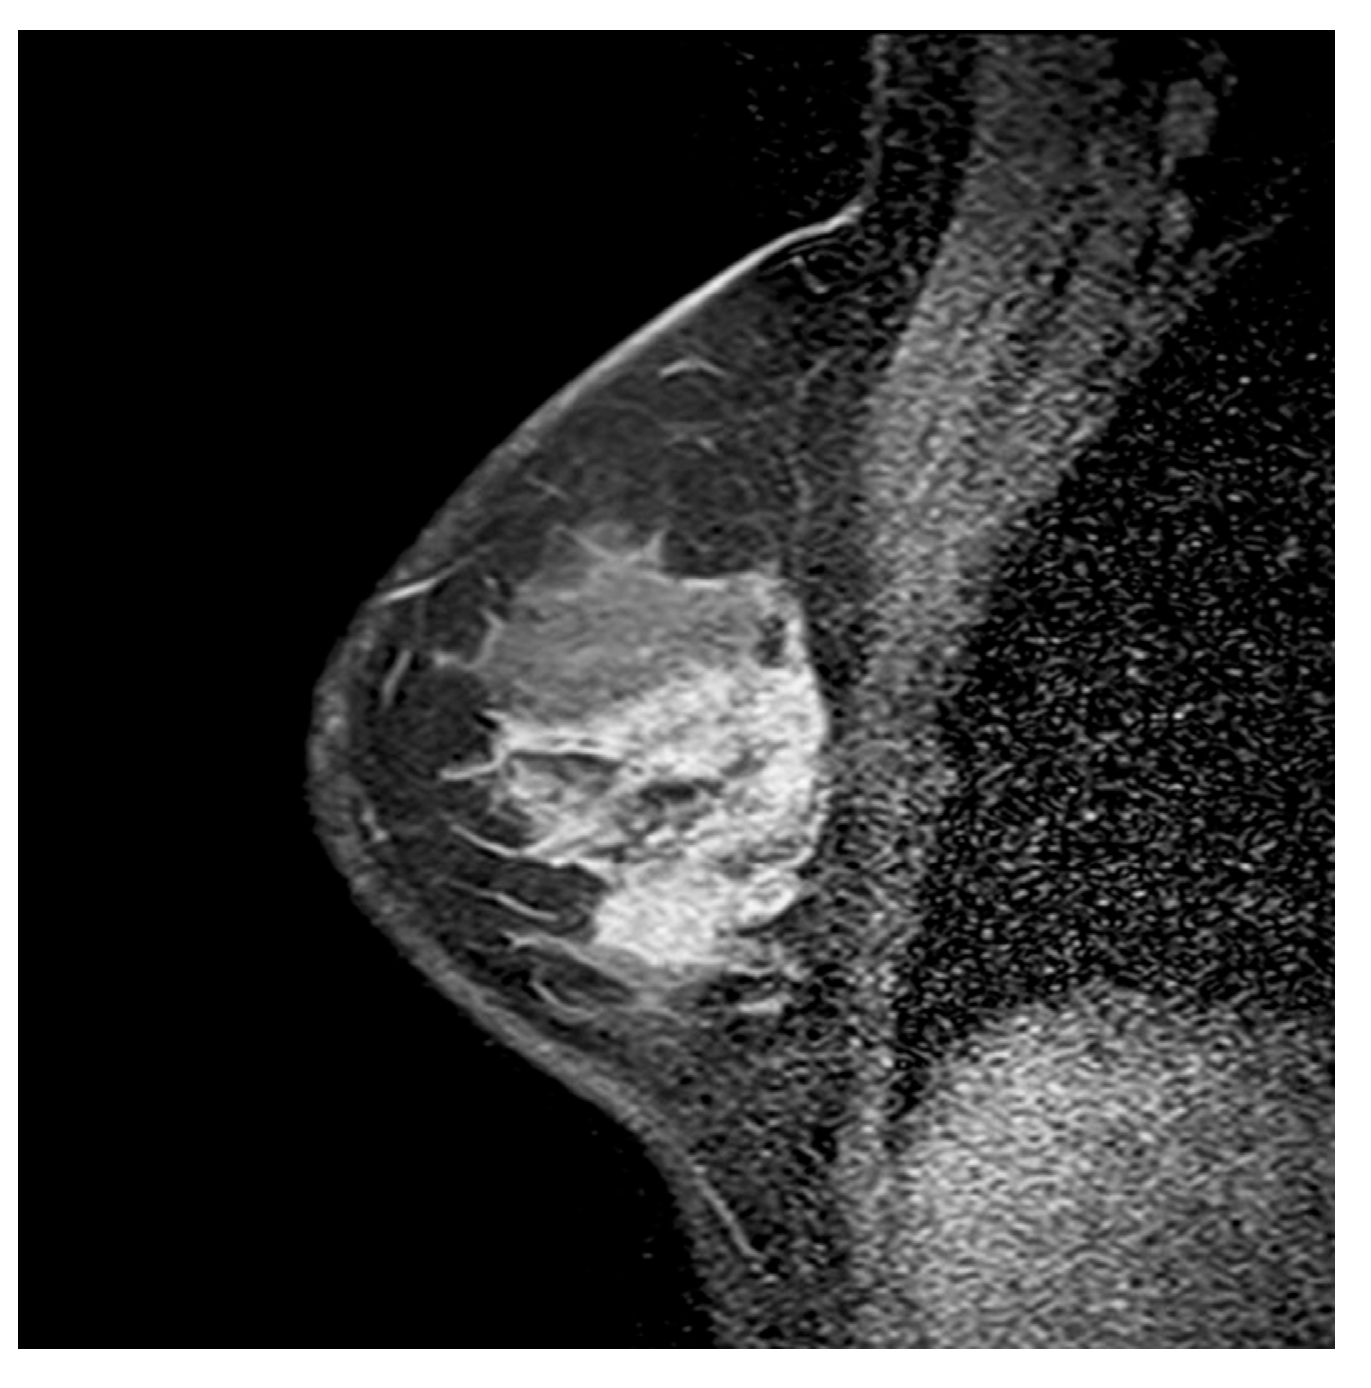

3.2.1. Internal Enhancement Patterns

3.2.2. Mixed Enhancement Patterns